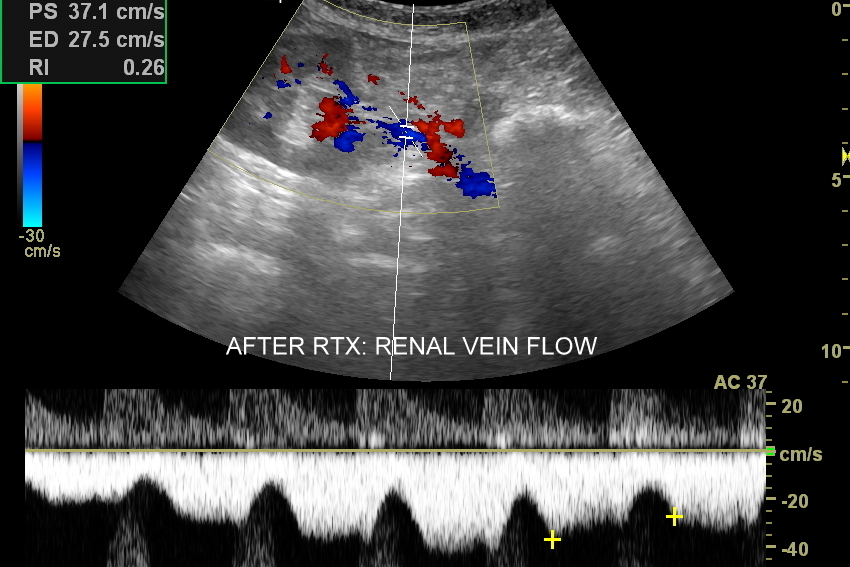

W Interdyscyplinarnej Pracowni Ultrasonograficznej dr Tomasza Szczepańskiego wykonają Państwo także kompleksowe badanie USG nerki przeszczepionej. Badanie to obejmuje wizualną ocenę sonograficzną nerki; ocenę jej lokalizacji pod kątem powikłań chirurgicznych; ocenę zespoleń tętnicy, żyły nerkowej oraz moczowodu; ocenę żywotności miąższu nerki i ewentualnych cech odrzucenia przeszczepu. Badanie USG nerki przeszczepionej jest procedurą multiparametryczną, tj. wymaga użycia takich modalności obrazowania jak color-Doppler, Doppler spektralny, obrazowanie mikrounaczynienia tkankowego, czasami także zastosowania USG z kontrastem CEUS. Do badania niezbędna jest również wysokospecjalistyczna wiedza oraz doświadczenie lekarza.